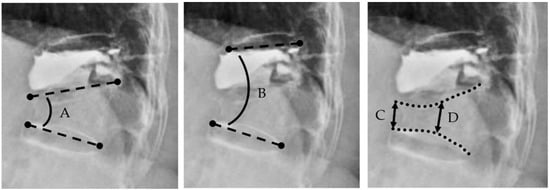

| Kyphotic deformity (°) | |||||

| Single kyphotic angle ‡ | 13.4 ± 9.7 | 8.6 ± 7.0 | 10.3 ± 9.1 | <0.01 | 0.05 |

| Two-segment kyphotic angle § | 15.6 ±11.8 | 12.6 ± 10.0 | 15.2 ± 10.1 | 0.02 | 0.03 |

| Vertebral body height (cm) | |||||

| Anterior vertebral body height | 1.9 ± 0.7 | 2.2 ± 0.6 | 2.3 ± 0.6 | <0.01 | 0.2 |

| Mid vertebral body height | 1.7 ± 0.5 | 1.9 ± 0.5 | 1.9 ± 0.5 | <0.01 | 0.8 |